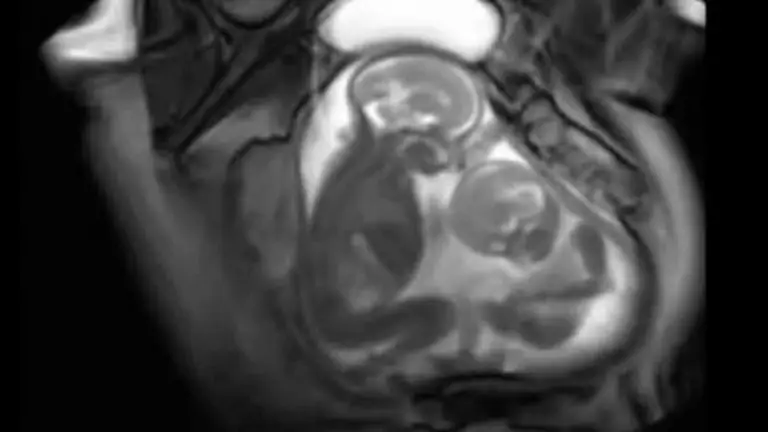

Mientras le hacían la resonancia magnética a una madre se logró capturar la pelea entre sus gemelos pateándose entre sí en el vientre de su madre, lo que significa que probablemente las rivalidades entre hermanos vienen desde que están en la barriga.